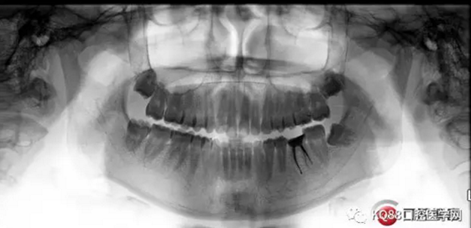

一周后復(fù)診,無明顯不適。擬樁,全冠修復(fù)。

12.png

首先預(yù)備樁道,樁道預(yù)備完成,用樹脂封閉根管口。嵌入兩根纖維樁。樁核粘結(jié)劑做基。

13.png

3M樹脂修復(fù)缺損。舌側(cè)電刀切齦,暴露齦壁,修整,制備。單線排齦,取模。

下次戴上全鋯全冠,整個治療修復(fù)過程就完成了。